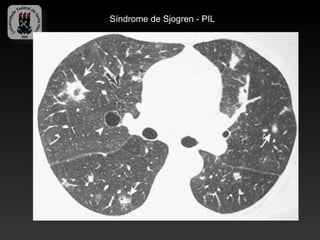

-SÍNDROME DE SJOGREN

-Caracterizada: ceratoconjuntivite seca, xerostomia e desordens do tecido

conjuntivo.

-Manifestações pulmonare: fibrose intersticial, doenças de pequenas vias

aéreas, PIL, linfoma MALT.

-Achados TC (PIL):

-   Atenuação em vidro fosco

-   Lesões císticas

-   Nódulos centrolobulares

-   Espessamento intersticial

Síndrome de Sjogren

Síndrome de Sjogren - PIL